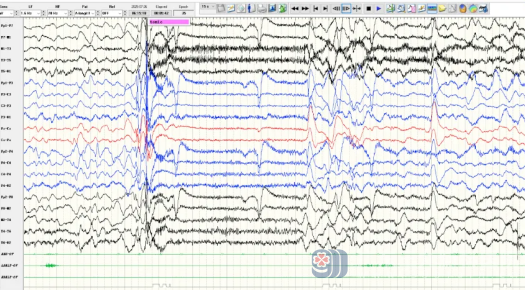

患儿近期脑电图

我院神经内三科(癫痫内科)徐铮主治医师接诊了患儿后,详细了解了患儿病史,复查脑电图显示背景较前明显变慢,放电较前明显增多,发作形式也较前有所改变。结合检查结果,徐铮明确诊断患儿为癫痫(伦诺克斯-加斯托综合征)、认知功能障碍。给予调整药物治疗方案的同时,邀请心理科医生会诊,针对患儿情绪、行为问题给出治疗方案。